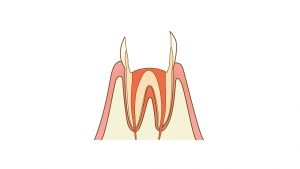

神経の近くまで達した虫歯です。まずは一般的な治療法から。

保険の治療ですと神経を保存できると判断できた場合はインレー形成といい、通常は金属の詰め物を入れます。自由診療でセラミックスを入れることもあると思います。健全な歯を削るため深い虫歯の場合問題なく過ごせる時と術後に痛みが出る場合がございます。

残念ながら虫歯が神経に達して神経の保存ができないと判断された場合は神経を取る処置を行い、土台をたて被せものをします。保険の場合は通常金属の冠また小臼歯や一定の条件を満たした大臼歯はハイブリッドセラミックスの白い被せものをします。自由診療ではセラミックスの被せものを選択できます。